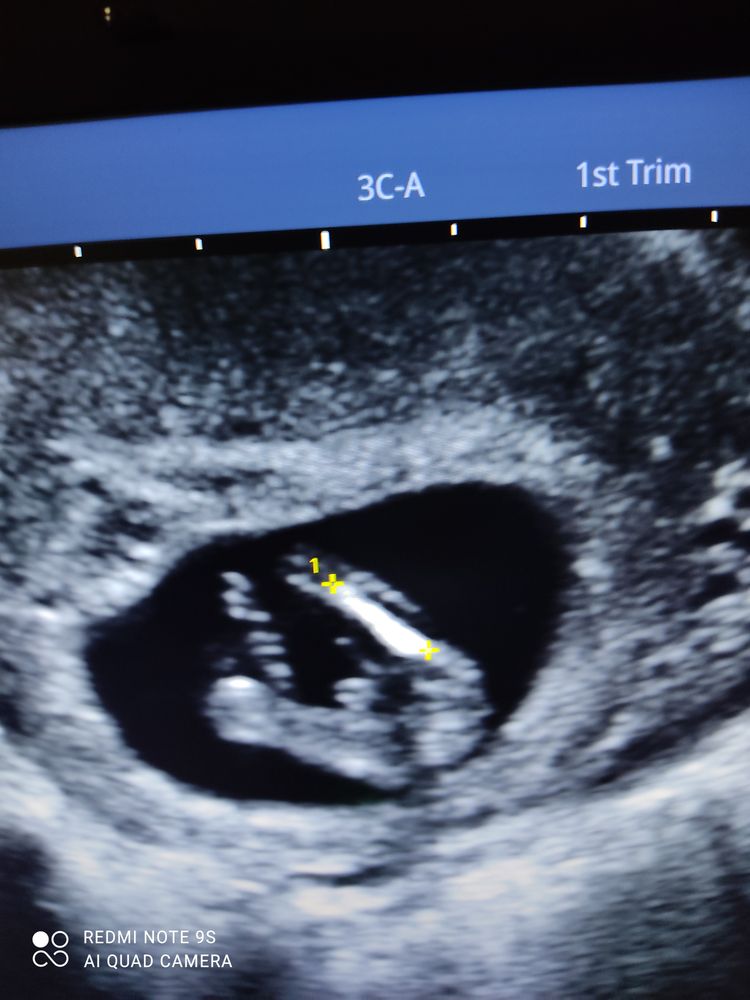

Мальчик???

На вашем сроке с этого ракурса у мальчиков и девочек все одинаково, надо сбоку смотреть.

Нет, в 14 недель уже чётко различимо, где мальчик, а где девочка.

Как по мне, то там девчачий пирожочек. Во вторую беременность тоже смотрели между ножек, а не по половому бугорку. Примерно такая же картина была.

Я вижу совершенно точно попец, а все остальное закрыто не пойму чем. В вашем случае как раз 50/50,но я б сказала 49 парень и 51 девочка. Яичек не видно

Не знаю, мне кажется мальчик)) где все увидели пирожок...не понимаю

На девочку похоже. Ибо не писюна, не машонки нет. И это пирожок

Пирожок девчачий 🧐

Сказали мальчик 🤐🤐🤐 ой посмотрим. )))

Слишком большой причиндал для такого срока 😀 Скорее всего какая-то другая часть тела. В 15 неделек уже будет видно пол на узи.